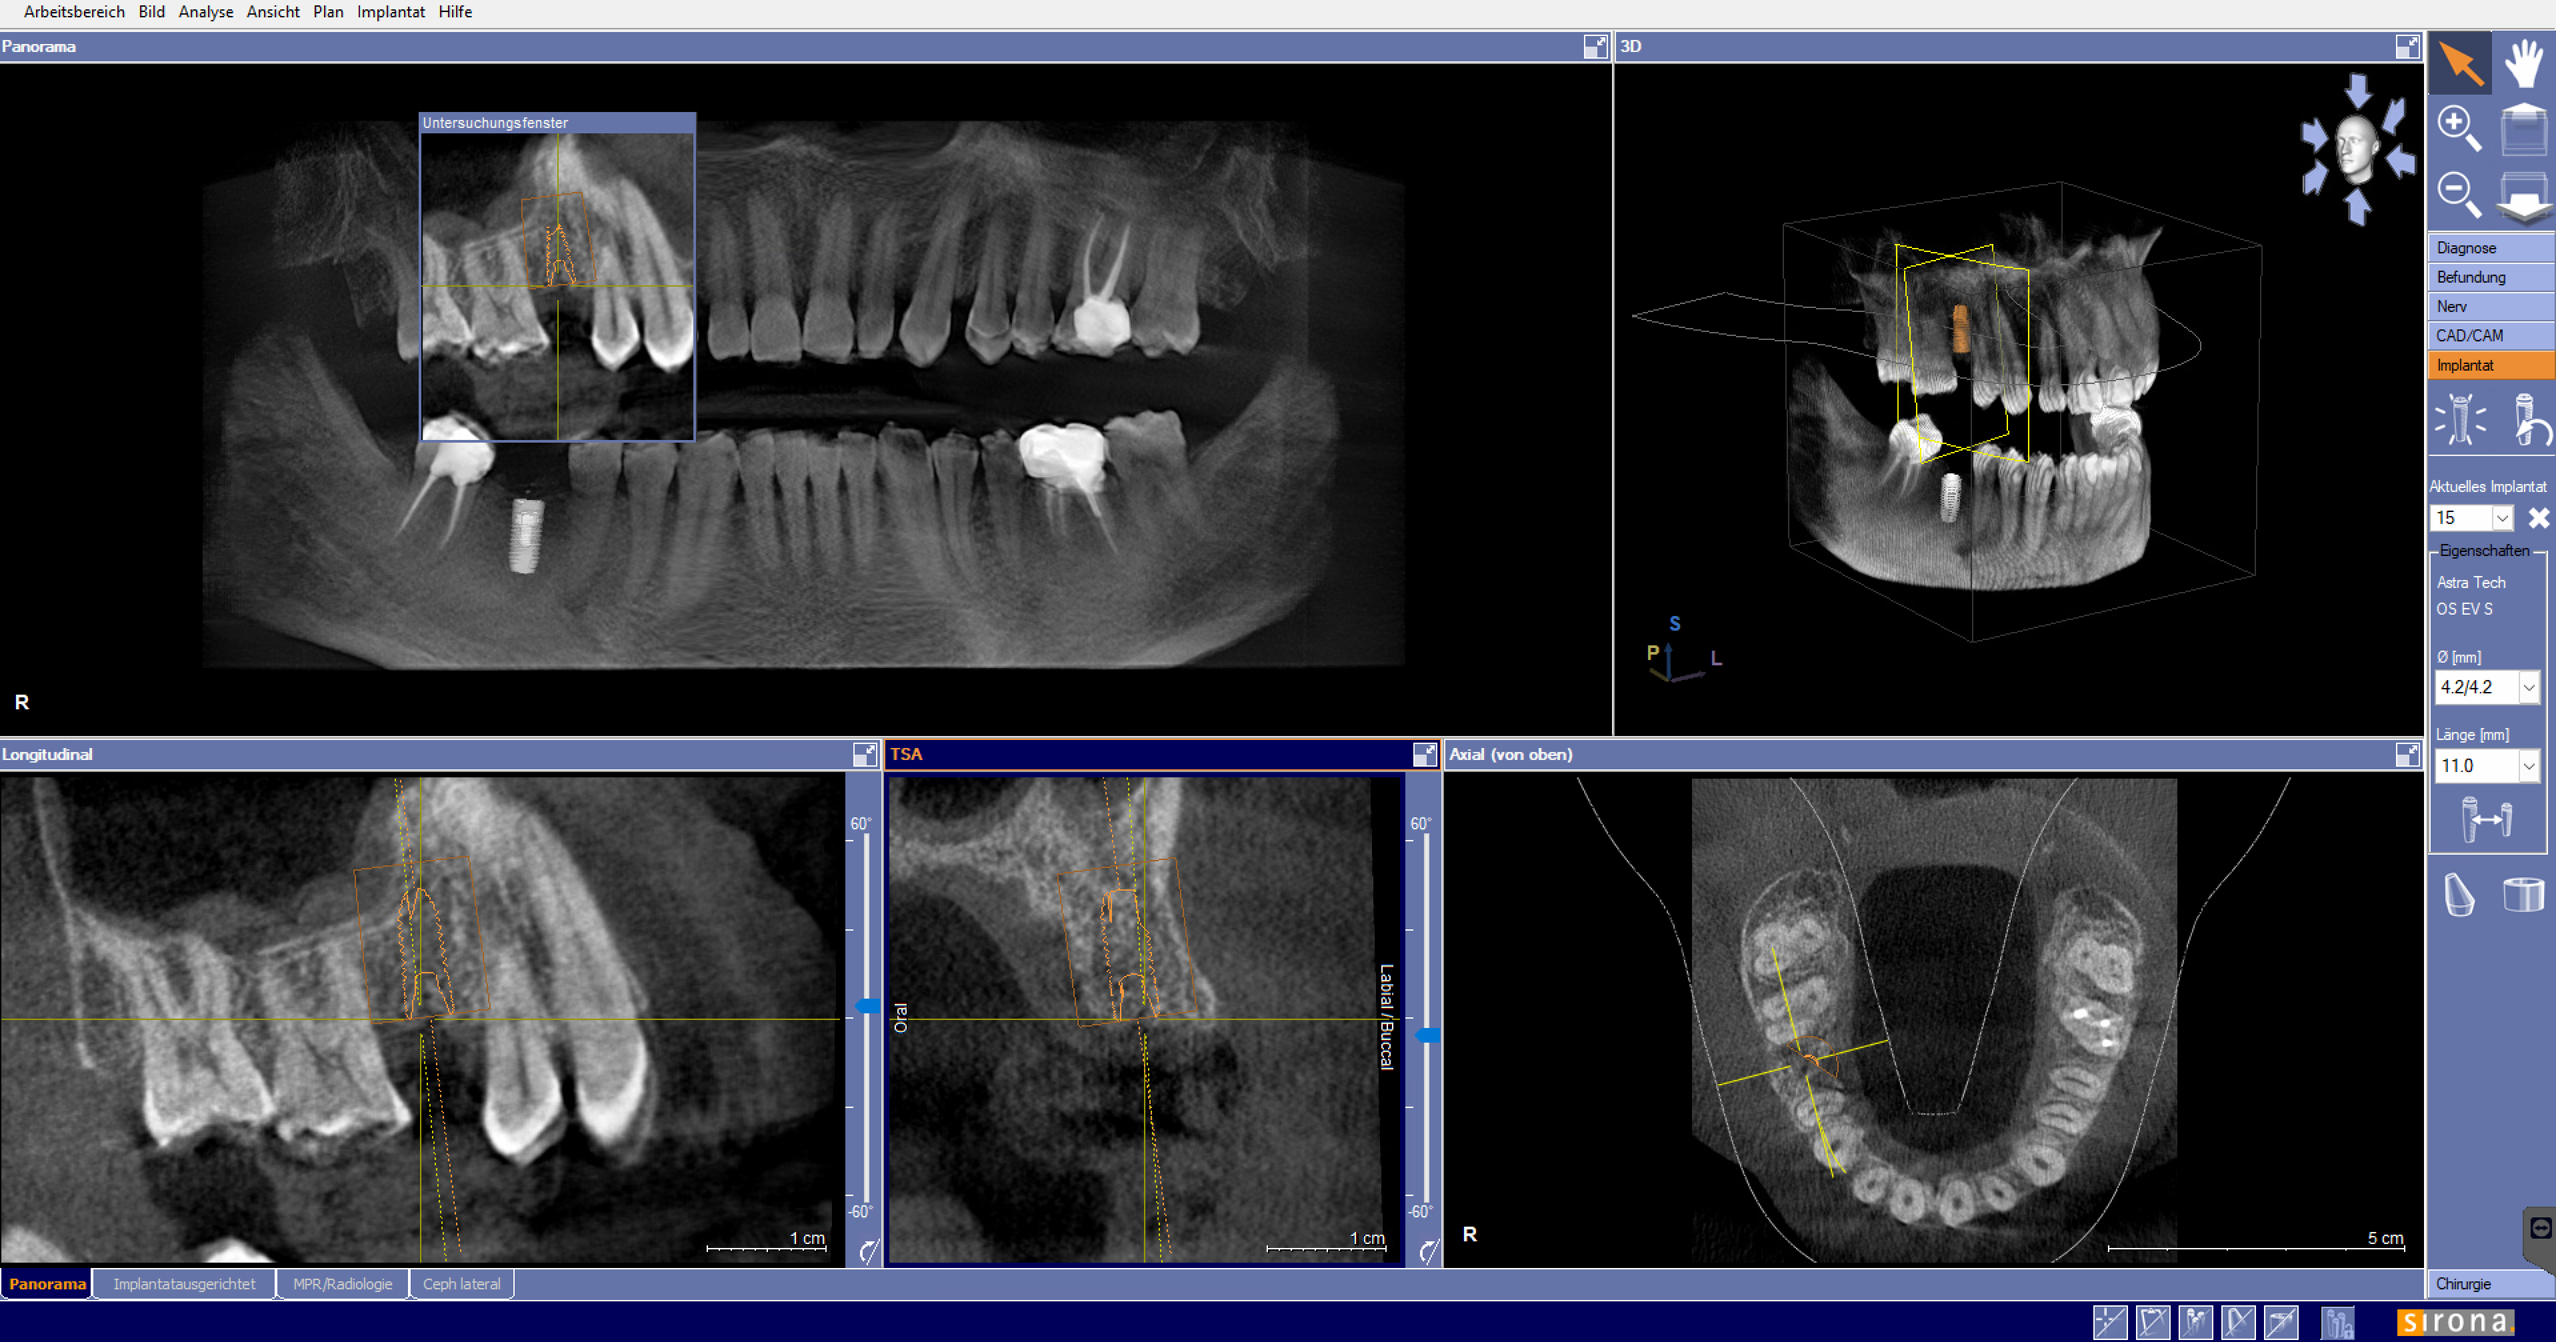

Bei der Planung von Zahnimplantaten ermöglicht die dreidimensionale Darstellung die genaue Einschätzung von Knochenhöhe und -breite, die Erkennung von Engstellen sowie die Beurteilung der Nähe zu sensiblen anatomischen Strukturen wie Nervenkanälen oder der Kieferhöhle. Implantate können dadurch millimetergenau positioniert werden, was ihre langfristige Stabilität und Funktion sichert.

Die DVT-Aufnahme dient entweder zur besonderen Herddiagnostik, als Grundlage für die OP-Planung oder als Mittel zur Verlaufskontrolle nach einem Eingriff. Dank der modernen Software können Schnitte durch die Kieferstruktur in beliebigen Ebenen erzeugt, Nervverläufe visualisiert und Implantatpositionen exakt simuliert werden.